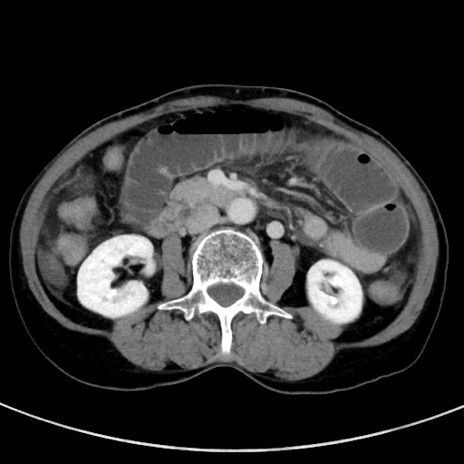

冠状断像

【症例】70歳代女性

【主訴】下腹部痛・嘔吐

【現病歴】2日前より腹痛あり。昨日嘔吐あり。症状改善しないため来院。

【既往歴】胃GISTに対して胃部分切除後。

【身体所見】BT 37.1℃、BP 128/77mmHg、腹部:平坦・軟、下腹部に圧痛あり。

【データ】WBC 10200、CRP 0.31